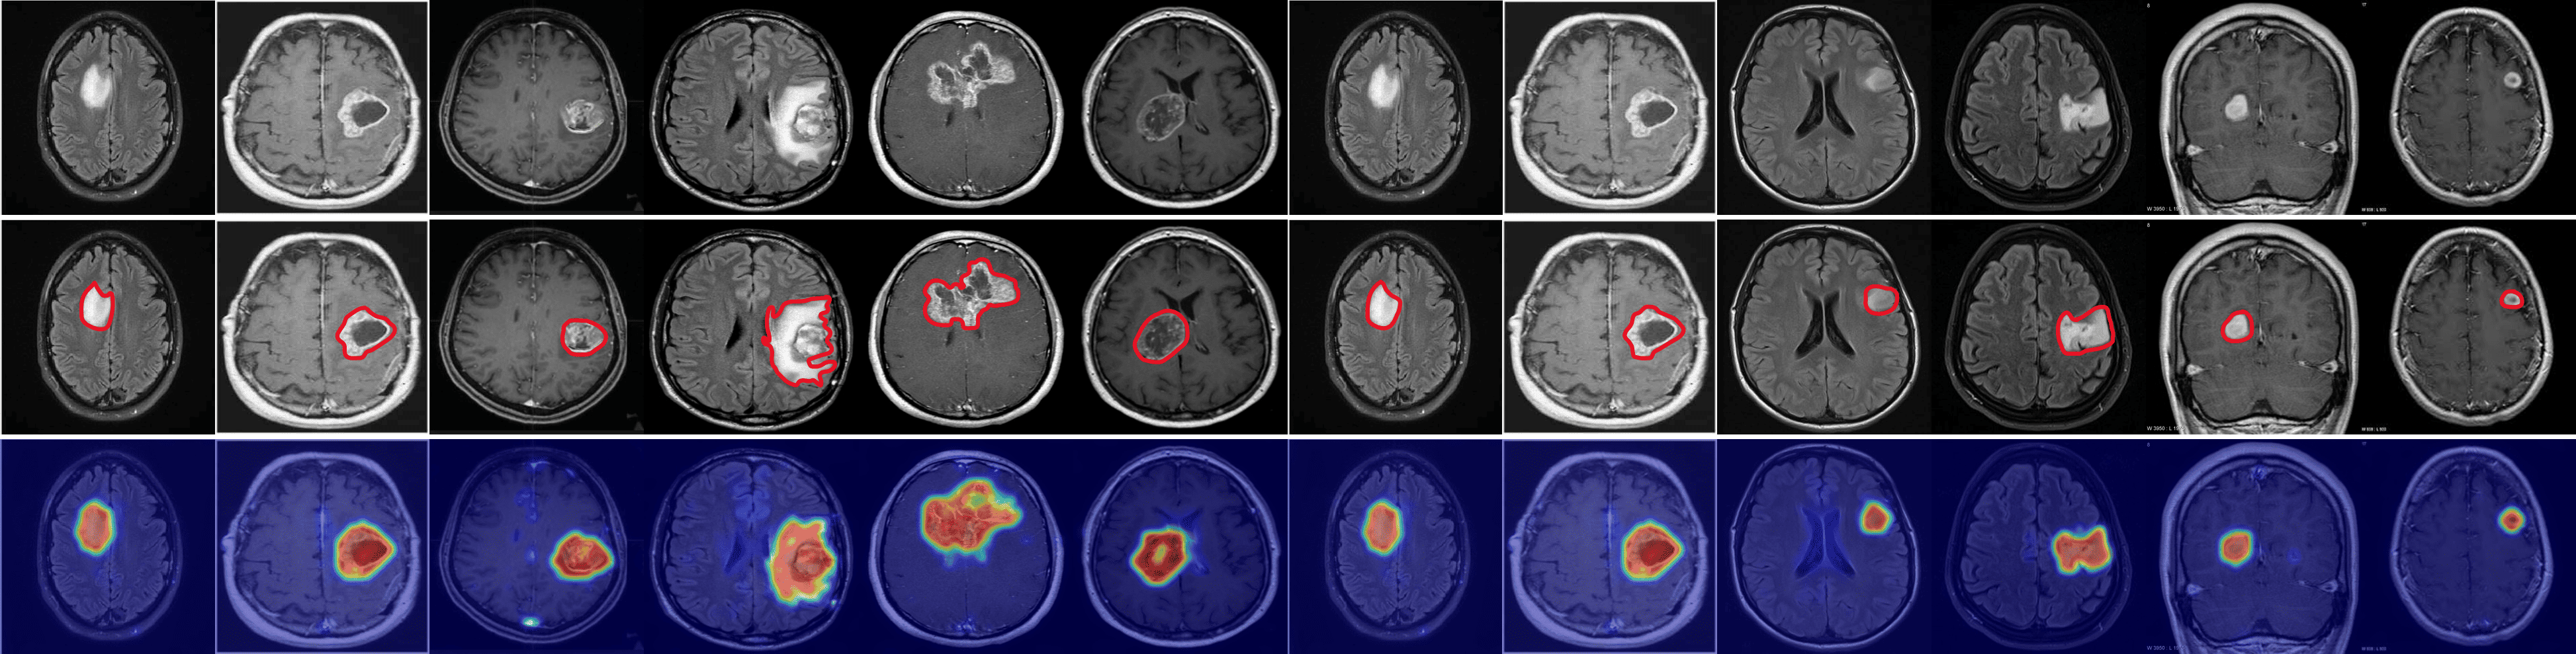

Refer to caption

Figure 3: Comparison of ZSAD results across industrial and medical domains. The first row displays input images from the industrial domain (Hazelnut, Bottle, Metal plate, Leather, Pcb1, Blotchy, and Electrical commutators) and the medical domain (HeadCT, BrainMRI, Endo). The second row presents the ground truth anomaly regions for each image. The remaining rows show the anomaly heatmaps generated by different models: CLIP, WinCLIP, CoOp, AnomalyCLIP, AdaCLIP, and GlocalCLIP.

Qualitative comparison

Fig. 3 shows a comparison of anomaly localization maps across the test domain datasets. In the industrial domain, images containing various defect types, such as hazelnuts, toothbrushes, bottles, metal plates, leather, pcb1, and blotchy. CLIP, CoOp, and WinCLIP struggle to capture fine-grained local anomaly regions. CLIP misinterprets normal and anomalous regions, demonstrating the need for adjustment in ZSAD applications. AnomalyCLIP demonstrated reasonable performance; however, it occasionally failed to capture certain anomaly regions that required a broader global perspective. In the medical domain, visualization results from the HeadCT, BrainMRI, and Endo datasets. CLIP and CoOp faced difficulties detecting anomalies, and while AdaCLIP performed well in certain cases, it failed to fully capture defects in some medical images. The explicit separation of global and local prompts in GlocalCLIP enables it to learn the distribution of normal and anomalous samples independently, and then enhance complementary learning, resolving the trade-off between image- and pixel-level performances caused by a lack of complementary information. Consequently, GlocalCLIP achieves the best ZSAD performance across both industrial and medical domains, demonstrating its generalization capability.